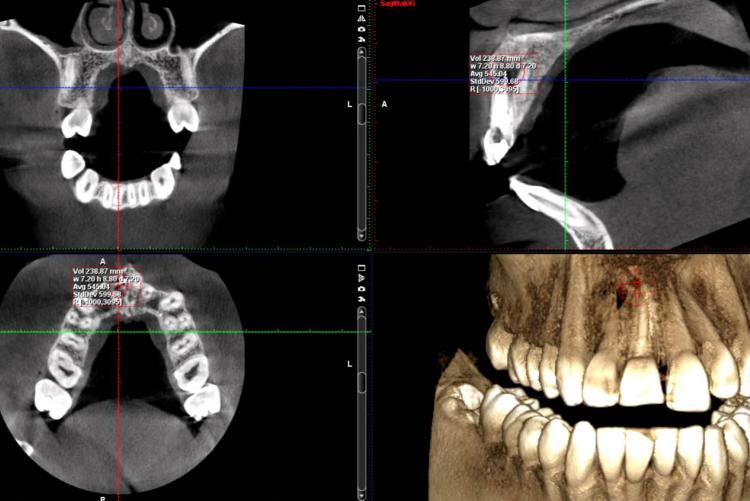

Conventional intra-oral radiography provides clinicians with cost-effective, high-resolution imaging that continues to be the front-line method for dental imaging. However, it is clear that there are many specific situations where the 3-D images produced by CBCT facilitates diagnosis and influences treatment. The usefulness of the CBCT cannot be disputed. It is a valuable task-specific imaging modality, producing minimal radiation exposure to the patient and providing maximal information to the clinician.